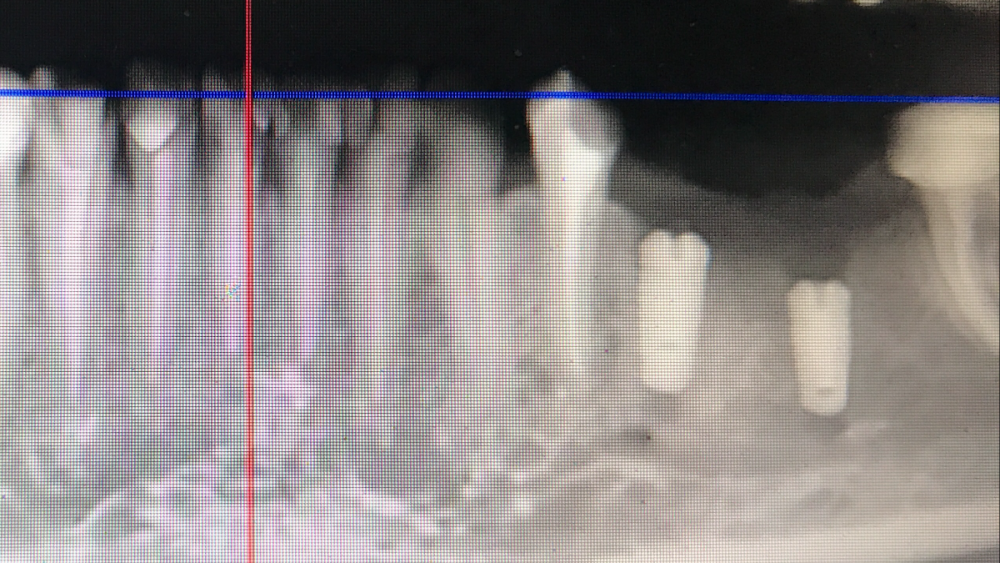

chealena Опубликовано 14 августа, 2021 Поделиться Опубликовано 14 августа, 2021 Здравствуйте ! В среду мне установили 4 импланта по две на каждые стороны нижние, слева также удаляли зуб и туда сразу ставили имплант. После этого у меня сейчас онемевшая губа и часть зубов и часть подбородка, что мне делать? Врач говорит что все нормально и нерв не был задет, а я вижу что на кт снимке идёт траншея до нерва , как будто он просверлил туда. Говорит мне ничего не делать и просто ждать. Но онемение не проходит, уже и отёк спал , а онемение есть и это ужасно противно, и когда пальцем вожу по этому месту очень неприятно как будто песок. Зуб слева первый имплант на снимке. Подскажите пожалуйста что делать! Ссылка на комментарий

Irouil Опубликовано 16 августа, 2021 Поделиться Опубликовано 16 августа, 2021 15.08.2021 в 00:45, chealena сказал: Но если нерв не поврежден почему у меня пол губы немые вместе с подбородком и частью зубов? Воздействия на нерв не ограничиваются только его повреждениями. Даже отёк от проведённой операции способен создать иногда достаточную компрессию чтобы вызвать транзиторную парестезию. Импланты в канал не пенетрируют, это самое главное. Руками хирурга тут особо нечего изменить/исправить. Применение физиотерапевтических процедур может ускорить реабилитацию. 2 Ссылка на комментарий